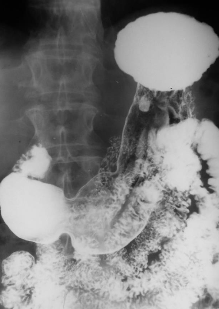

Neoplasm malign gastric vegetant